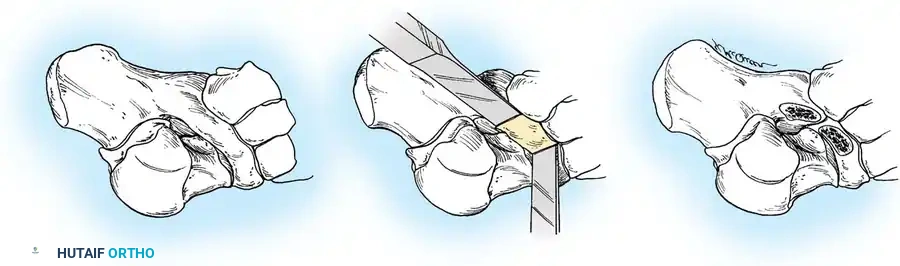

Ossicle Excision: Using sharp dissection, meticulously shell the accessory navicular out from the substance of the posterior tibial tendon. If transposition of the tendon is planned, attempt to leave a microscopic sliver of bone within the tendon to enhance subsequent bone-to-tendon healing.

Navicular Resection: Resect the medial prominence of the main navicular so that it is flush with the medial border of the first cuneiform. This is typically achieved using an osteotome, followed by a rongeur and rasp to smooth the cortical edges.

Tendon Advancement: Suture the PTT to the apex of the medial longitudinal arch. This can be achieved by utilizing local periosteum and ligamentous tissue to secure the transposed tendon slip, or by passing heavy non-absorbable sutures through drill holes placed in the center of the navicular and tying them dorsally.

- Biomechanical Reduction: Try to advance this slip of tendon while the talonavicular joint is anatomically reduced. Reestablish the medial longitudinal arch by holding the midfoot and forefoot in a cavovarus position during knot tying.

Advanced Imaging and Anatomical Reference Gallery

The following images illustrate various presentations, surgical exposures, and advanced imaging modalities (including CT and MRI correlates) utilized in the comprehensive evaluation and treatment of rigid pes planus and tarsal coalitions: